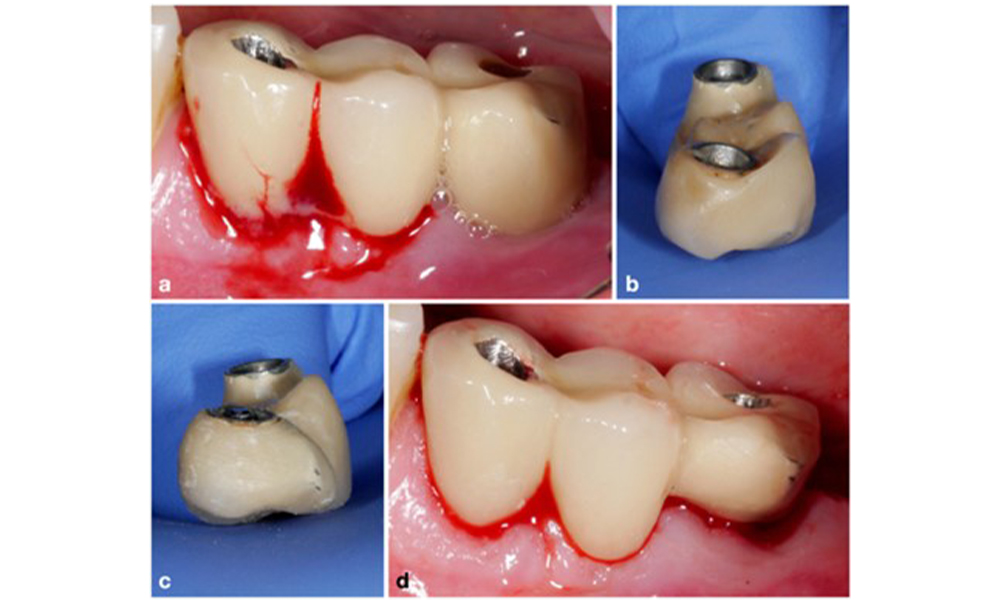

Le World Workshop on the Classification of Periodontal and Peri-Implant Diseases and Conditions de 2017 a établi des critères de diagnostic pour la mucosite péri-implantaire et la péri-implantite (Renvert et al. 2018). La mucosite péri-implantaire est définie comme (1) la présence d'une inflammation autour de l'implant (c'est-à-dire une rougeur, un gonflement, une ligne ou une goutte de saignement dans les 30 secondes suivant le sondage), associée à (2) l'absence de perte osseuse supplémentaire après la cicatrisation initiale (figure 1).

La péri-implantite est identifiée par (1) des signes d'inflammation similaires à la mucosite, (2) des preuves radiographiques de perte osseuse après la cicatrisation initiale et (3) une augmentation de la profondeur de sondage par rapport aux mesures prises peu après la mise en place de la reconstruction prothétique (figure 2). En l'absence de radiographies antérieures, un niveau osseux radiographique de ≥ 3 mm, accompagné d'un saignement au sondage et d'une profondeur de sondage ≥ 6 mm, indique une péri-implantite.